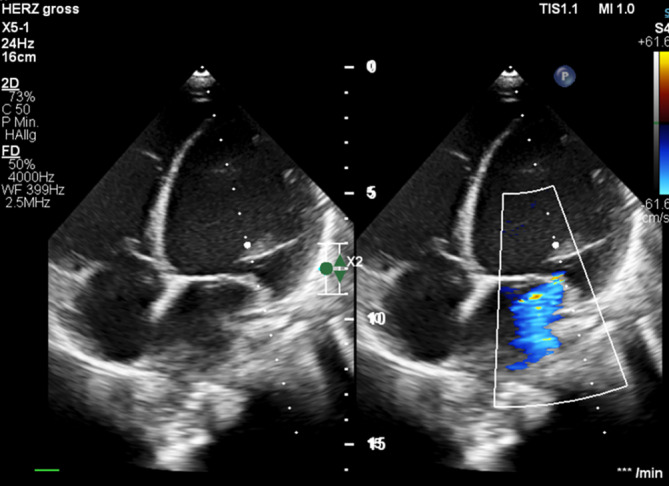

A 9-year-old girl presented with slight deterioration in her general condition over the preceding 2 weeks. She was referred by her pediatrician due to bilateral eyelid edema, hepatomegaly on palpation and cough persisting for 2 days. Chest X‑ray revealed cardiomegaly. Echocardiography showed left ventricular (LV) dilation (LV end-diastolic diameter 57 mm) with second-degree mitral valve insufficiency (Fig. 1). LV contractility was severely impaired (fractional shortening [FS] 12%, LV dP/dt 630 mm Hg/s). Correspondingly, laboratory tests revealed an elevated NT-proBNP level of 12,006 pg/ml (normal range 8–178 pg/ml). Relative to her severely impaired ventricular function, the patient presented with a surprisingly stable general condition with only mild symptoms. The family history was unremarkably. Cardiac magnetic resonance imaging (MRI) confirmed echocardiographic findings, demonstrating an end-diastolic LV volume of 203 ml (188 ml/m2; reference range: 60–70 ml/m2) and an LV ejection fraction (LV-EF) of 16%. The right ventricle (RV) was also dilated, with an end-diastolic volume of 120 ml (112 ml/m2; reference range: 62–72 ml/m2) and a reduced RV-EF of 35%. There was no evidence for late gadolinium enhancement (LGE).

Fig. 1.

Echocardiography on admission. Note left ventricular dilatation and mitral valve insufficiency